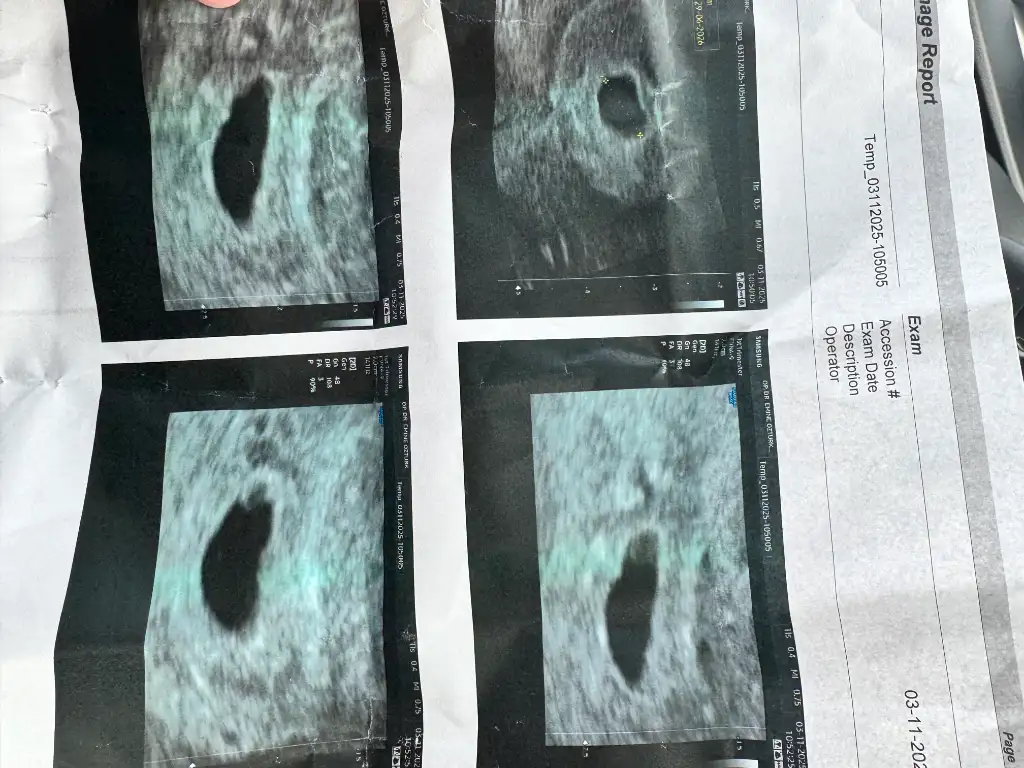

Merhaba benimde adetim gecikince test yaptım evde pozitif çıktı Ella içmiştim ama şüphelendiğim gün için Ella ama öncesinde de 3 gün çnce yine şüphe duyup içmedim bir şey lafın kısası test pozitif çıktı kanda da sonra hemen kontörle gittim kese göründü içi boş lekelenmem olunca 5 gün sonra tekrar gittim yine boş bir Hafta bekleyelim dedi 7+3 dü sanırım yani 9 mm kese inşAllah boş gebeliktir o zaman kürtaj yapacak ben hiç istemiyorum zaten eşimlede sıkıntılar yaşıyorum görsel ekleyeceğim ne olur yardımcı olun yarın öğreneceğiz net ama ben çok korkuyorum bebeği görmek istemiyorum inşAllah boştur dilerim Allah isteyene nasip etsin

7+3 için 9mm kese küçük sanırım boş olma ihtimali daha yüksek gibi, ama insanın başına gelince binde bir ihtimali sen yaşıyorsun

Benim kese 14 mm bugün gördü doktor ama bebek yok salı günü gel dedi eve geldim şuan da düşük yapıyorum